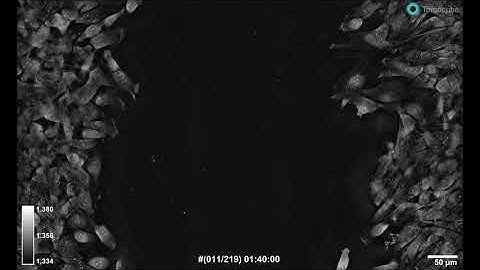

Label-free 3D Live Cell Imaging and Quantification using Holotomography